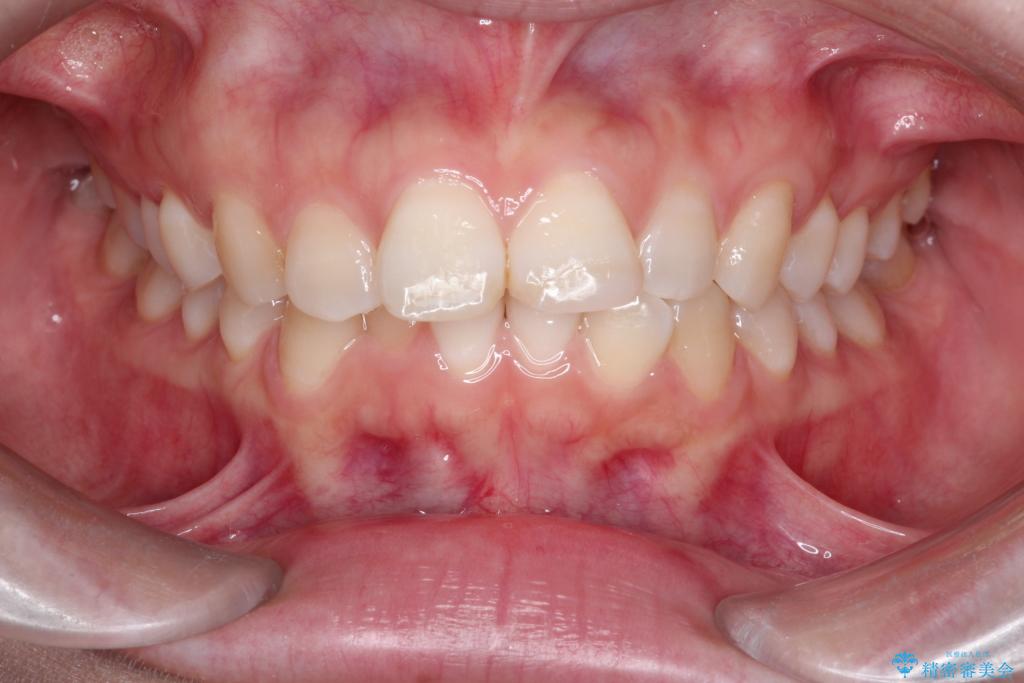

- 前歯のデコボコ(叢生)を気にされてご来院されました。精密な検査の結果、歯が並ぶスペースが不足していることが判明。患者様のご希望から、透明で目立ちにくいインビザライン(マウスピース矯正)による治療計画を立案しました。抜歯を避け、奥歯全体を奥へ動かす遠心移動という方法でスペースを確保し、前歯の叢生を解消することを目指します。

今回の矯正治療では、透明なマウスピース型の装置インビザラインを使用しました。この装置は取り外し可能で、日常生活で目立ちません。治療は、緻密に計算された計画に基づき、段階的に作製されたマウスピースを交換していくことで、奥歯から順に全体を後方へ移動させる遠心移動を実施。これにより、前歯を並べるための十分なスペースが確保され、デコボコが解消されました。抜歯することなく、機能的にも審美的にも整った美しい歯並びを獲得していただけました。